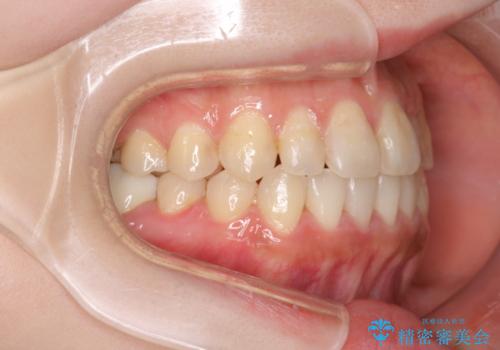

八重歯をインビザラインで非抜歯矯正

- 八重歯を主訴に来院されました。

インビザラインにて奥歯を後方に移動して八重歯が入るスペースを確保してく矯正する計画としました。

八重歯と前歯のガタガタがなくなり、歯並びがきれいになったのと、かみ合わせも改善することができました。